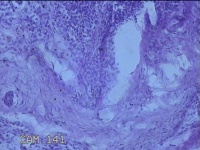

右侧颜面部结节

性别

男

年龄

41岁

临床诊断

皮下结节

一般病史

发现右侧颜面部结节20余年。

标本名称

大体所见

灰白暗红色组织1x0.3x0.2cm一个,表面带梭形皮肤1x0.3cm,皮下见结节0.8x0.3x0.2cm一个,切开挤呈实性,切面灰白粉红色,质中。